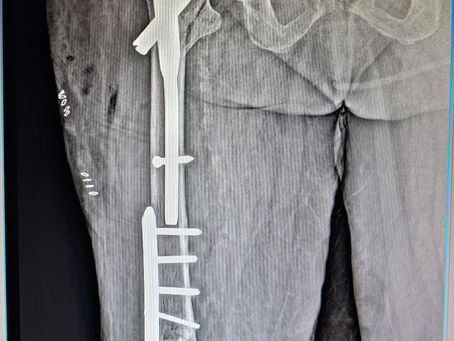

Clavicle fractures l, should be it be fixed or not??

Clavicle fractures transcends age and has been a subject of debate regarding whether they be fixed or not. While according to biomechanics of the clavicle fracture which has been traditionally been treated with a support,we are moving towards surgical option for each and every case which is not ethical . Other than getting a surgical practice, it is too dangerous as many fractures operated go for nonunion with plate acting as distractor. Clavicle fractures managed nonoperativ